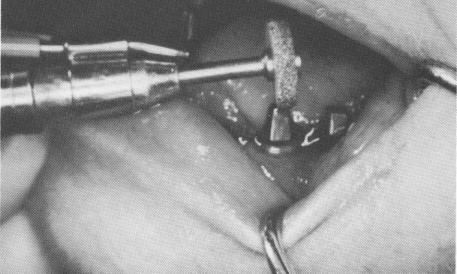

When bending the post is not adequate, further adjustments may be made in the mouth. To reduce a post's face, a fissure bur or tapered diamond stone with a water spray attachment may be employed. If the post is too tall, a heatless stone with a water attachment is used to shorten it (Fig. 7-46) .

Fig. 7-46. To adjust occlusal height and attain mesial distal parallelism, a heatless stone with a water spray attachment and a tapered bur may be used.